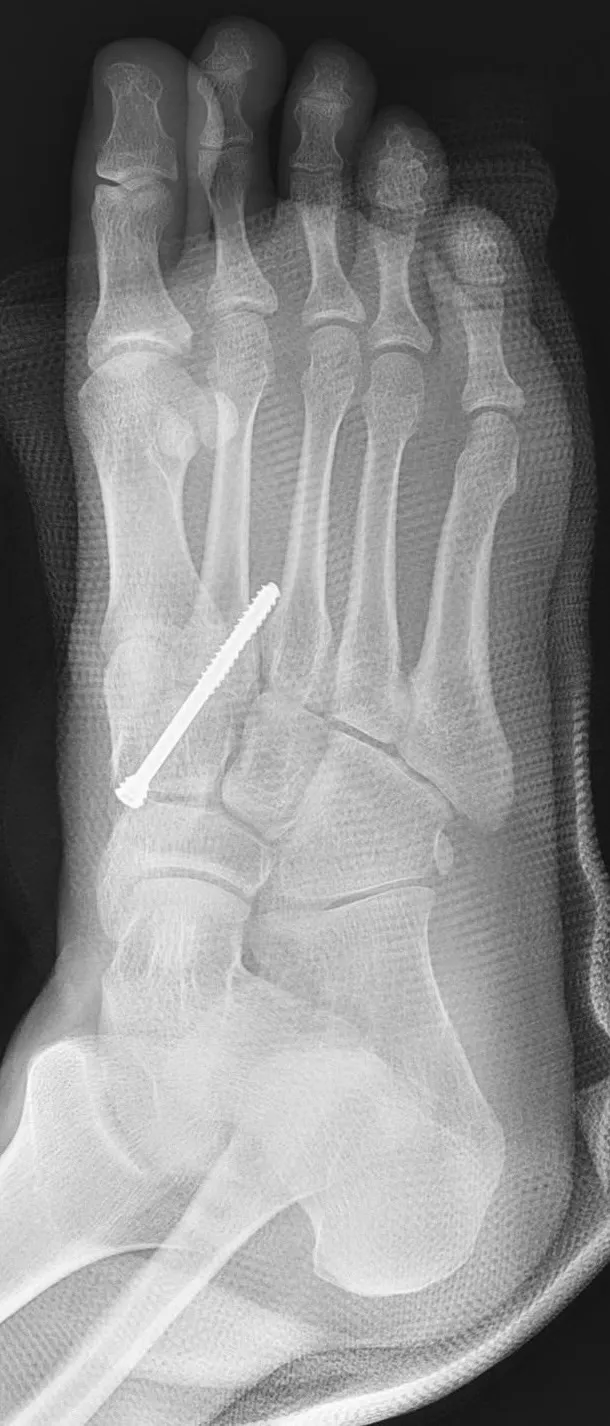

患者照X光發現,跗趾關節有開離。大里仁愛醫院提供